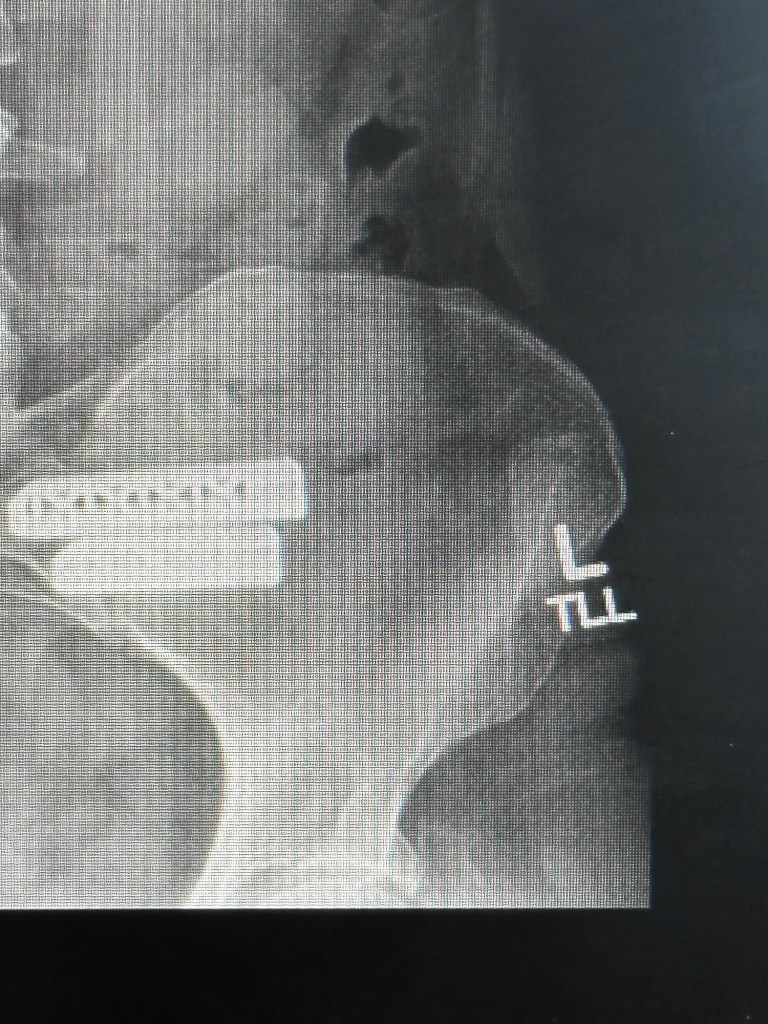

Lateral View of the three SI joint implants